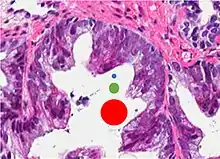

| Non acinar (or mixed acinar/ non-acinar) adenocarcinoma | Ductal adenocarcinoma | 3% to 12.7%[8][notes 1] | ![]() |

||||